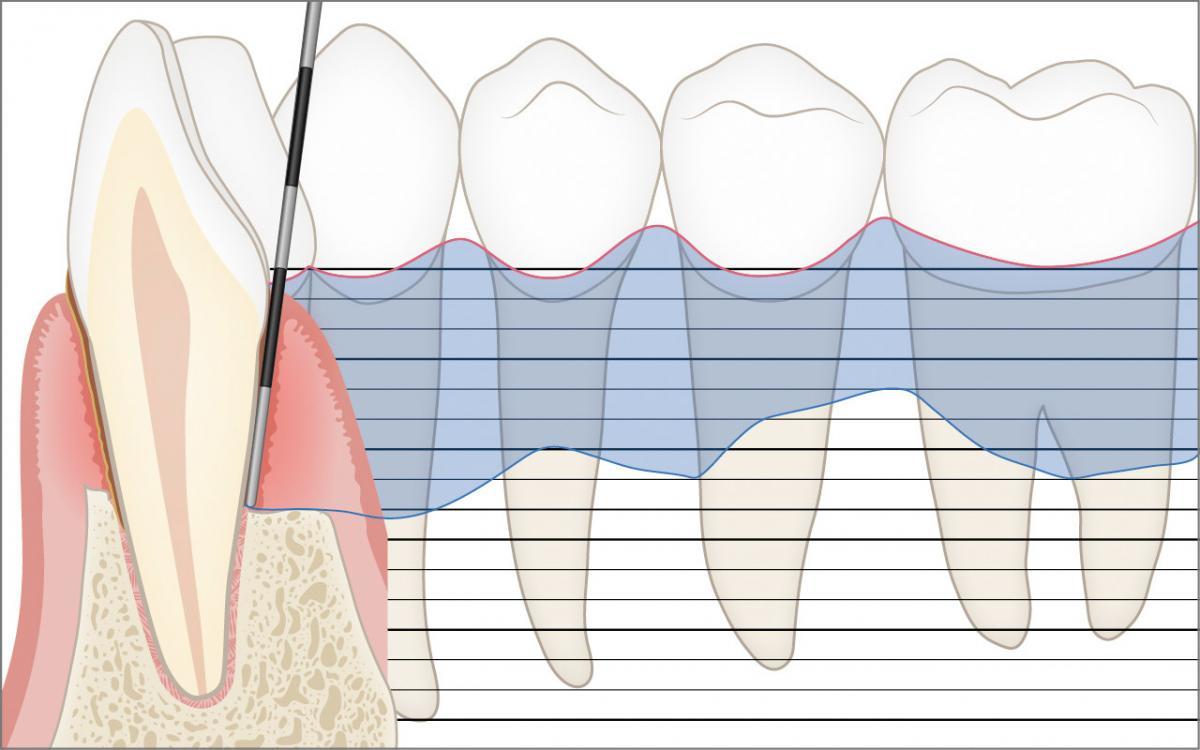

Parodontalstatus

Die millimetergenaue klinische Sondierung mit der Zahnfleischsonde zur Ausmessung der Zahnfleischtaschen und der Höhe des Kieferknochens sind zur Diagnose der Parodontitis unverzichtbar.

Zusätzlich wird in einem sogenannten Parodontalstatus die Höhe des Kieferknochens (Attachmentniveau) millimetergenau festgehalten. Ein Parodontalstatus ist zur Diagnostik und Behandlungsplanung einer Parodontitis unverzichtbar. Der Parodontalstatus kann in jeder Zahnarztpraxis online aufgezeichnet und weiterverwendet werden: www.parodontalstatus.ch.